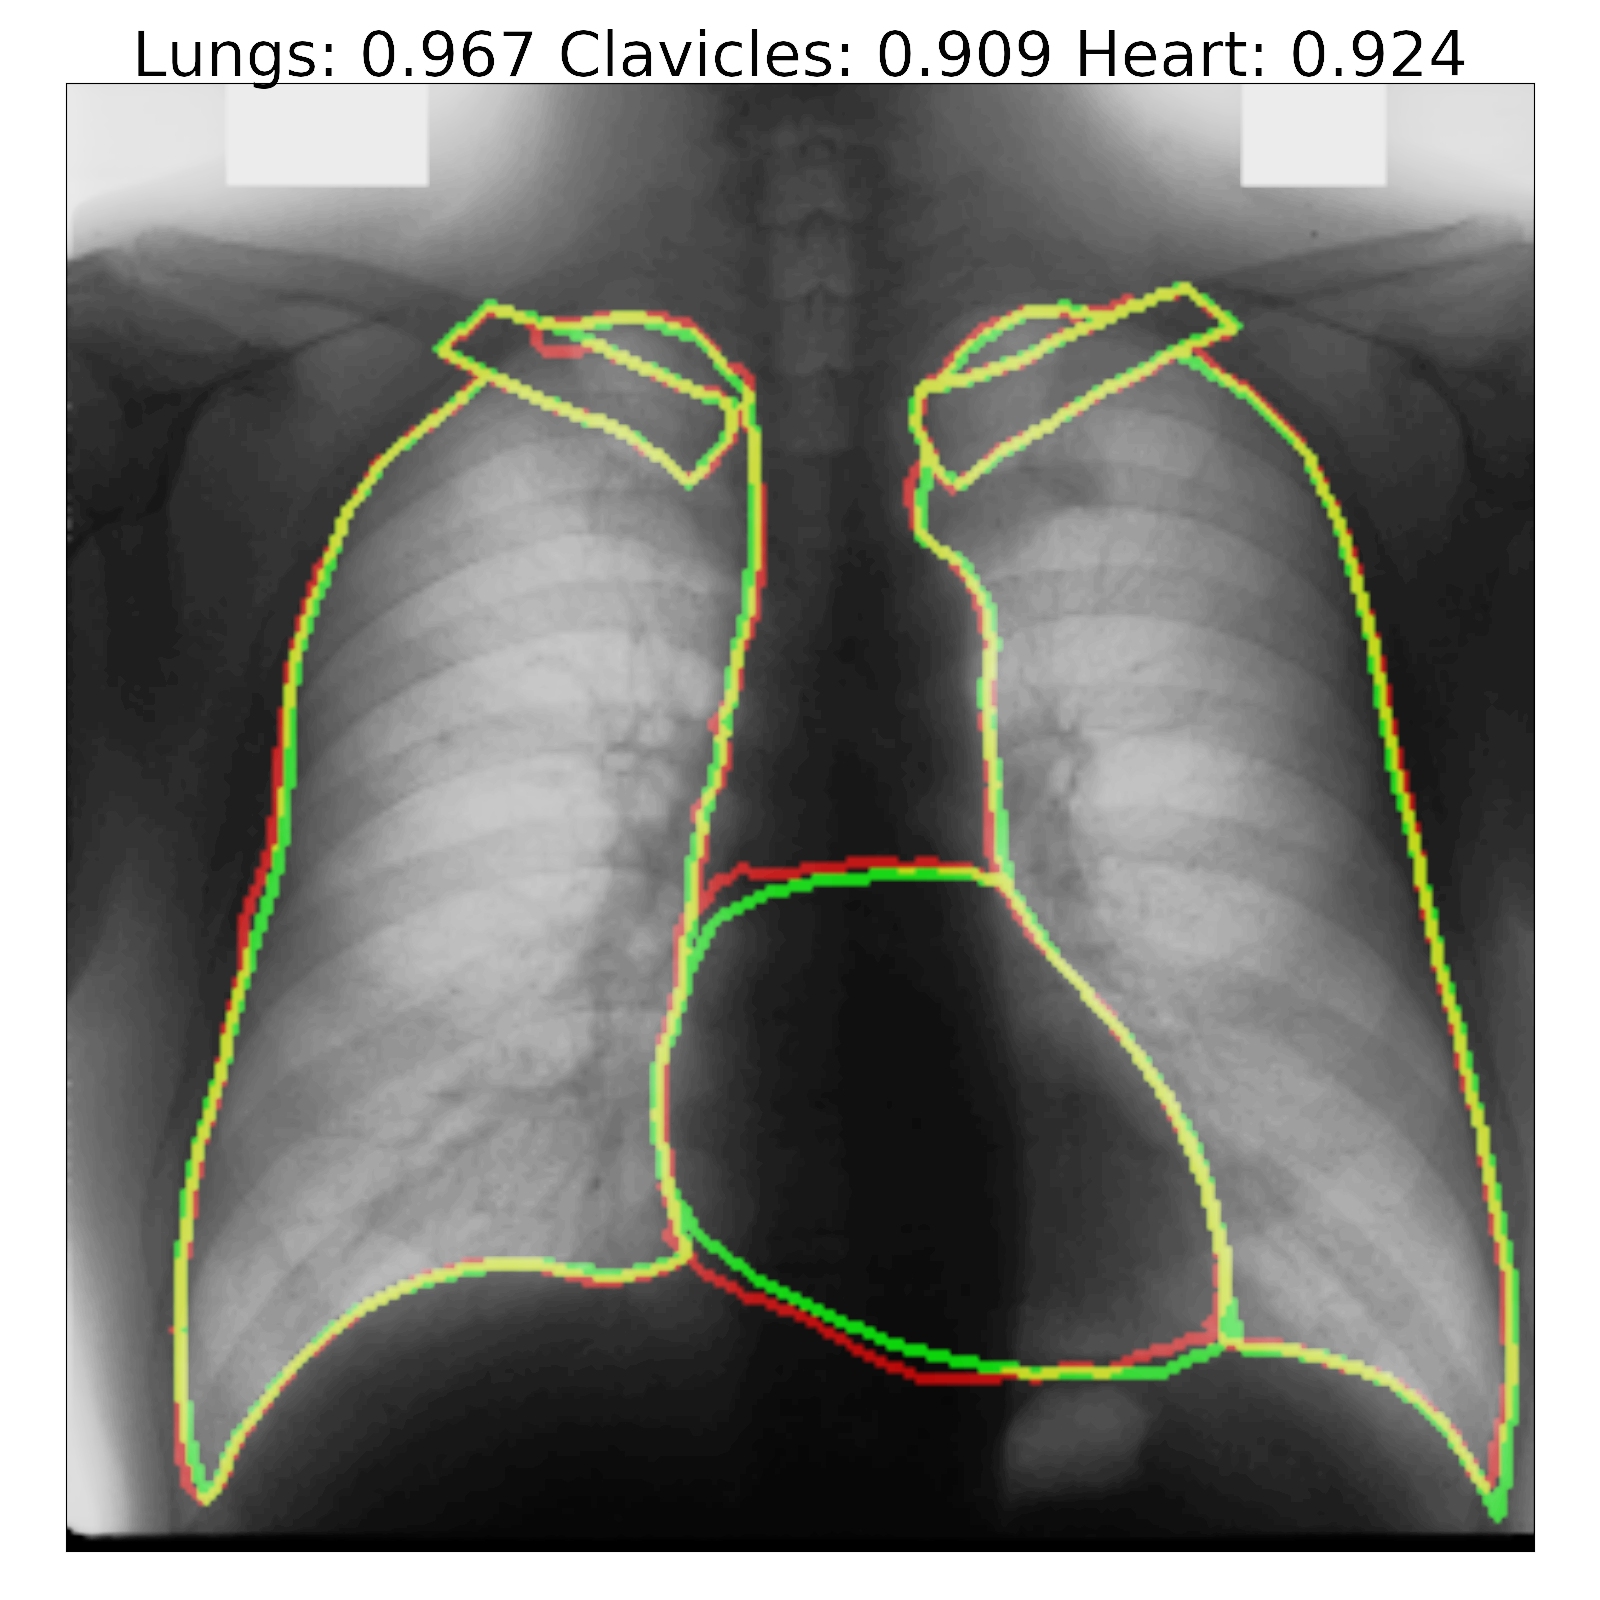

Figure 7: Segmentation results and corresponding Jaccard scores on some images for U-Net (top row) and proposed InvertedNet with ELUs (bottom row). The contour of the ground-truth is shown in green, segmentation result of the algorithm in red and overlap of two contours in yellow.

Fig. 7 shows a few examples of the algorithm results for both successful and failed cases for U-Net (top) and the InvertedNet  trained with the ELU and loss function based on the Dice coefficient. The white boxes show Jaccard scores for lungs, clavicles and heart. To extract the shape contours of the segmentation and ground-truth, we used a morphological outline extraction algorithm on both segmentation result and reference masks. The contour of the ground-truth is shown in green, the segmentation result of the algorithm in red and the overlap of two contours in yellow colors.